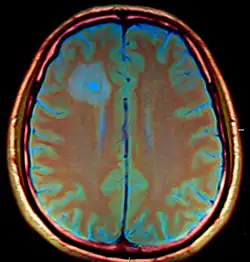

Brain abscess in a person with a CSF shunt. The abscess is the darker gray region in the lower left of the image (corresponding to the right parietal lobe). The lateral ventricles are visible in black in the center of the brain, adjacent to the abscess.[1] | |